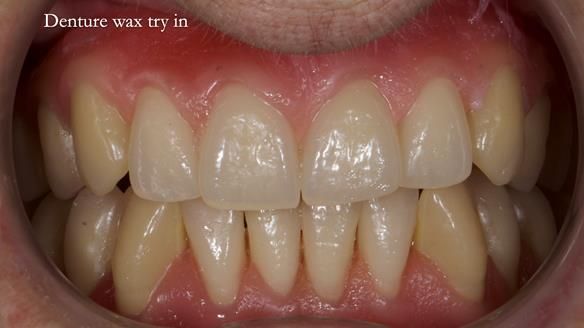

Welcome to Newsletter 83. This month I am sharing Sheila’s case — a very challenging but rewarding complete denture case. Sheila had flat ridges, a small mouth opening, a large tongue and had never been able to wear complete dentures of any kind. Everything was loose and sore. She felt embarrassed and looked older without dentures. She wanted a stable, comfortable result, and she wanted to avoid implants because she has taken bisphosphonates for more than five years.

In this newsletter I will take you through Sheila’s full protocol step by step — including impressions, French Impression Technique, Dr Abe shaping, copying Kirsty MacColl’s smile, the try-in, the final fit, and the copy dentures we made afterwards.